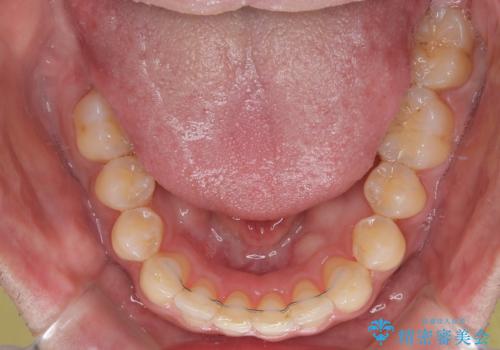

上顎前歯の舌側転位が顕著であったため、治療期間が長くなると思われましたが、僅か1年で無事に終えることができました。

- 矯正治療後の保定が不十分だと後戻り(元の位置に戻ろうとする動き)をします